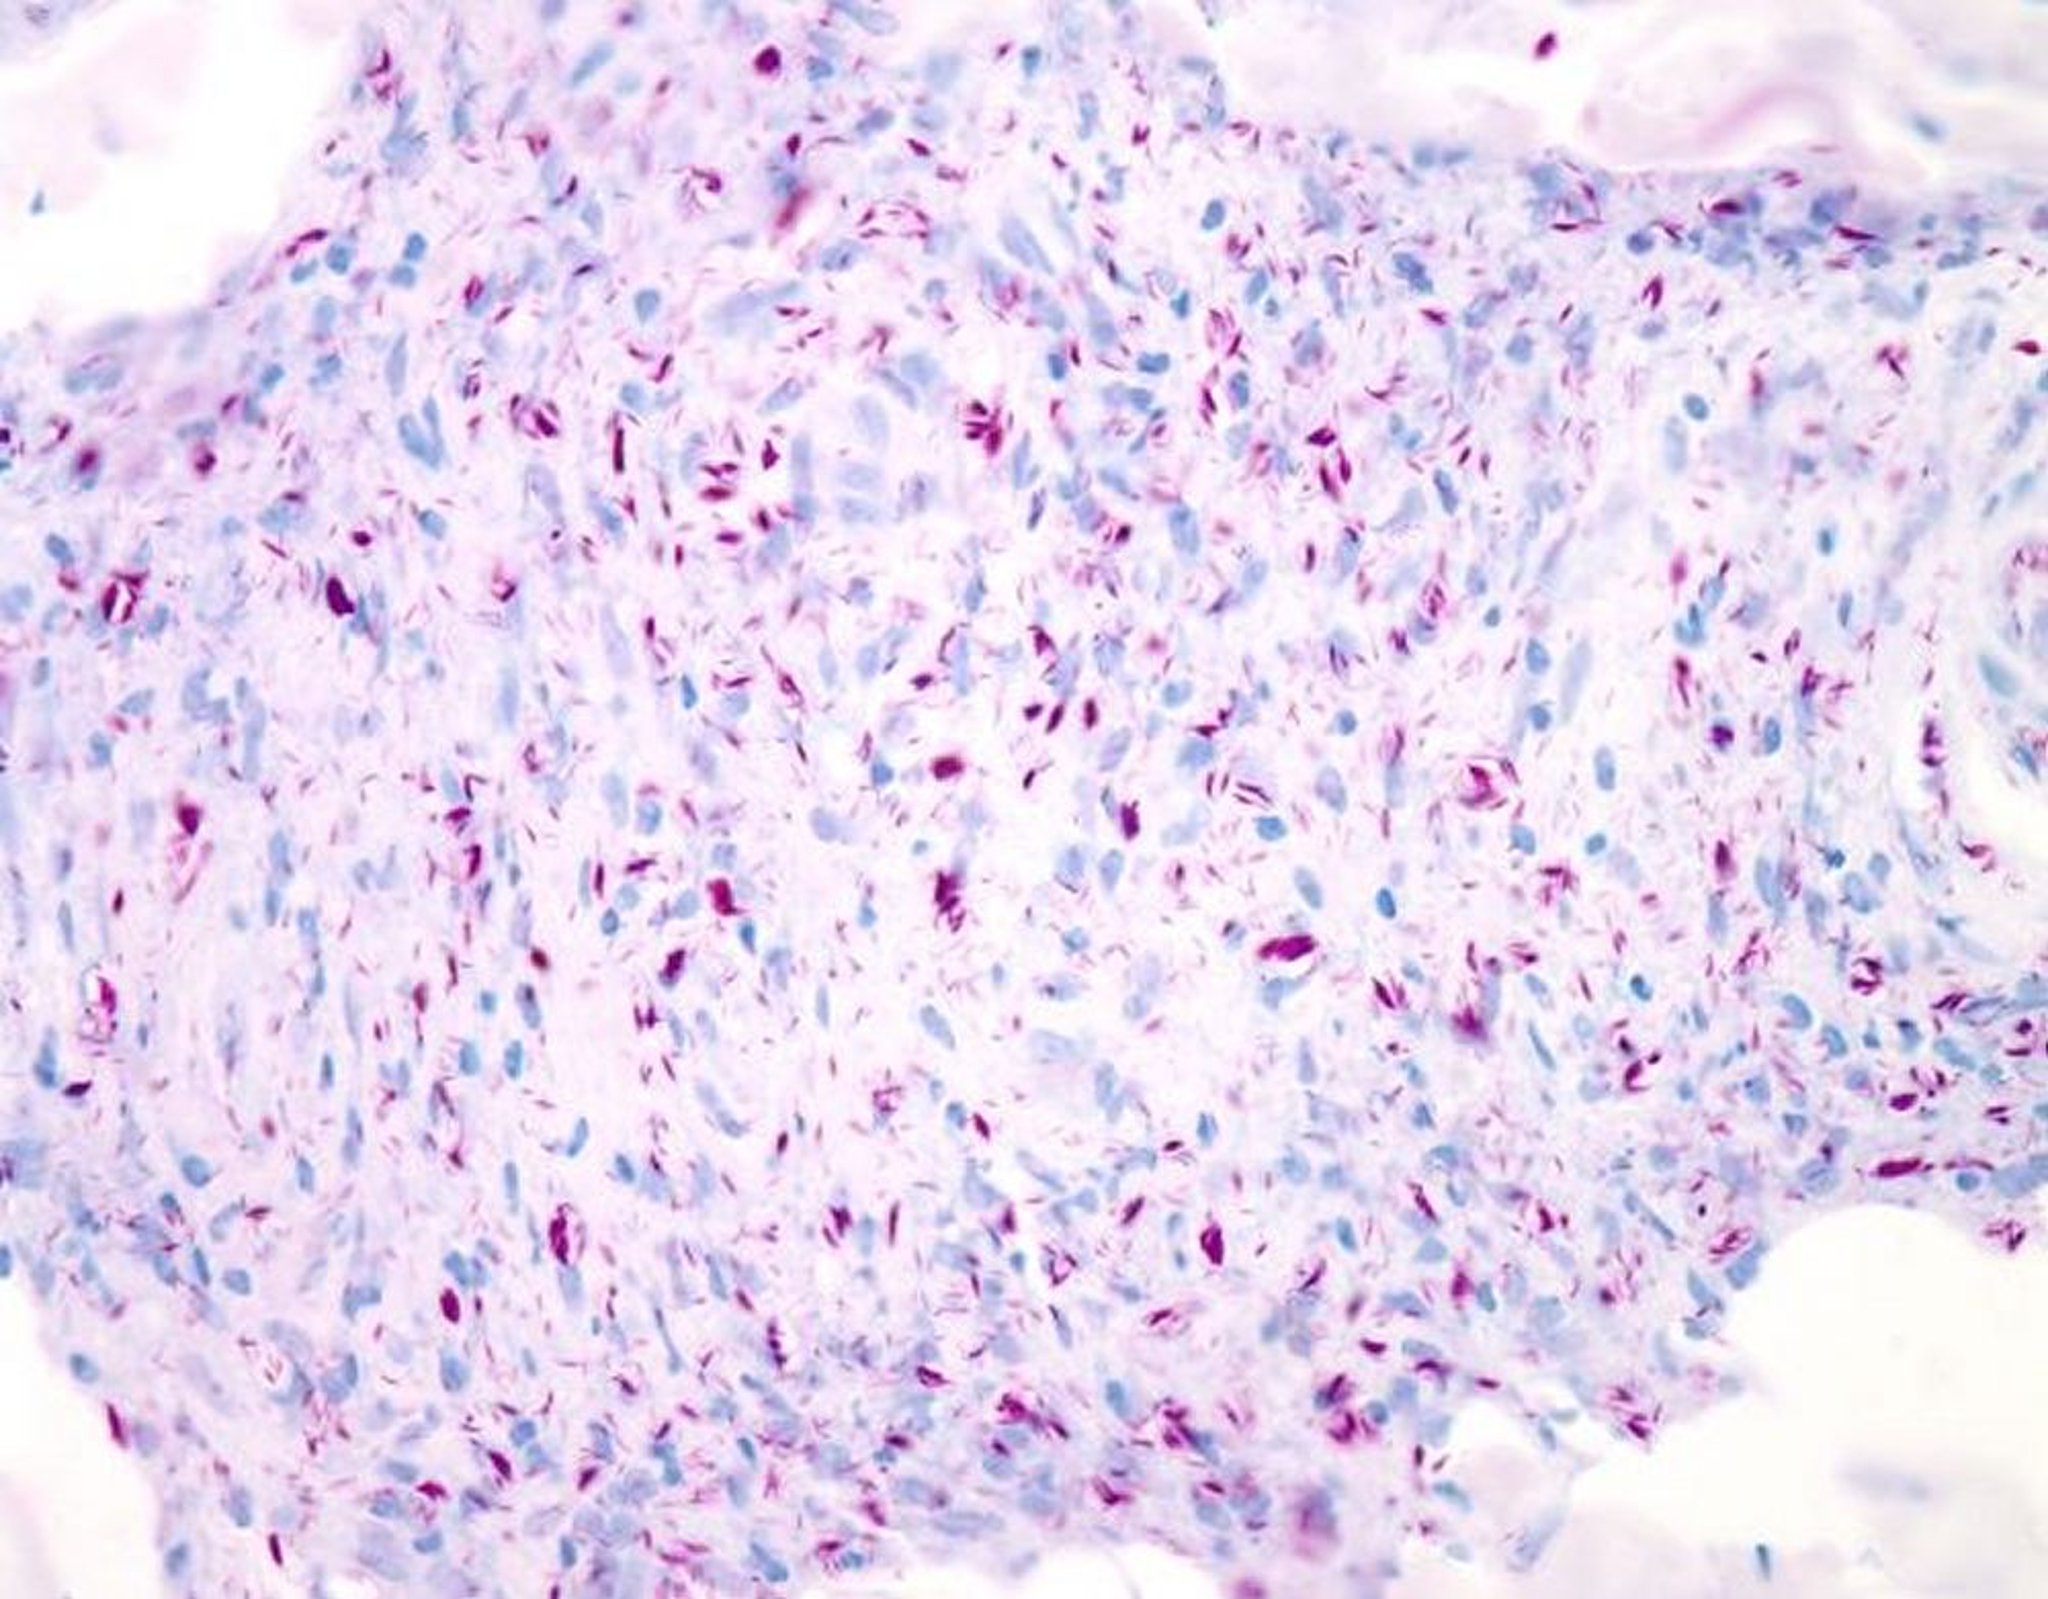

Coloration Ziehl-Neelsen de Mycobacterium leprae

Cette image est une micrographie optique sous coloration de Ziehl-Neelsen modifiée (coloration de Wade-Fite) de M. leprae d'une biopsie cutanée d'un sujet atteint de lèpre lépromateuse. Les mycobactéries apparaissent en rouge et sont présentes en grand nombre, isolément et en groupes (globi). Le grossissement est de 20X lors d'une impression en 10 cm de large.

WEBPATHOLOGY/SCIENCE PHOTO LIBRARY